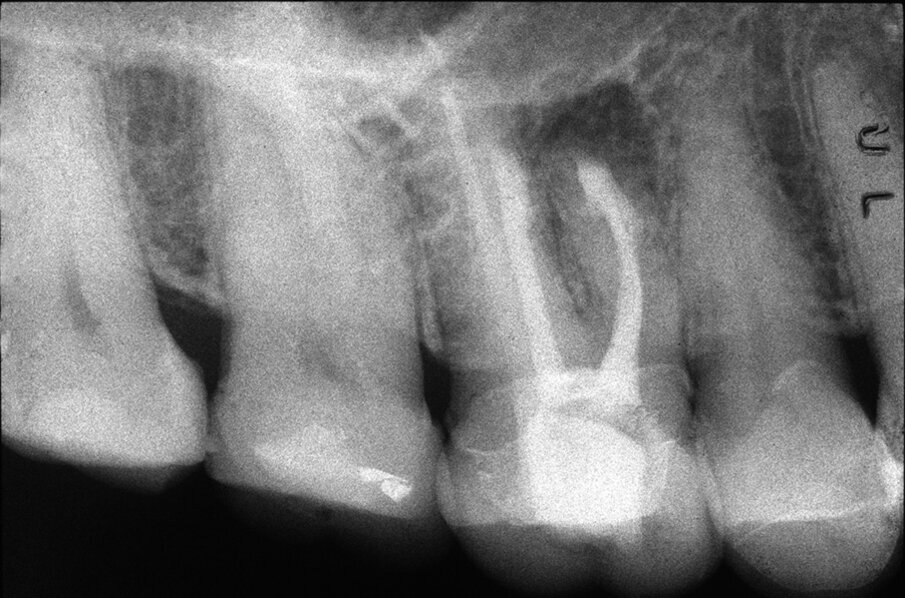

Tali perforazioni sono piuttosto frequenti a livello degli incisivi superiori, dove l’errore che più spesso viene commesso è rappresentato dall’utilizzo della fresa con eccessiva angolazione vestibolare. Perforazioni del terzo coronale possono anche accadere sul pavimento dei molari quando gli orifizi canalari vengono cercati in posti sbagliati. Tipiche sono le perforazioni nei molari superiori o inferiori, che avvengono per lo sfondamento del pavimento della camera pulpare (Figg. 3a-3i). Come conseguenza del trauma meccanico, si ha una rapida distruzione del legamento parodontale. L’osso alveolare immediatamente adiacente alla perforazione si riassorbe con conseguente perdita verticale di osso. Il processo infiammatorio quindi si estende coronalmente lungo le fibre del legamento parodontale, con distruzione del legamento, dell’osso alveolare e delle fibre gengivali sopracrestali. Come conseguenza di ciò, si ha la migrazione apicale dell’attacco epiteliale e le formazione di un grave difetto parodontale9.